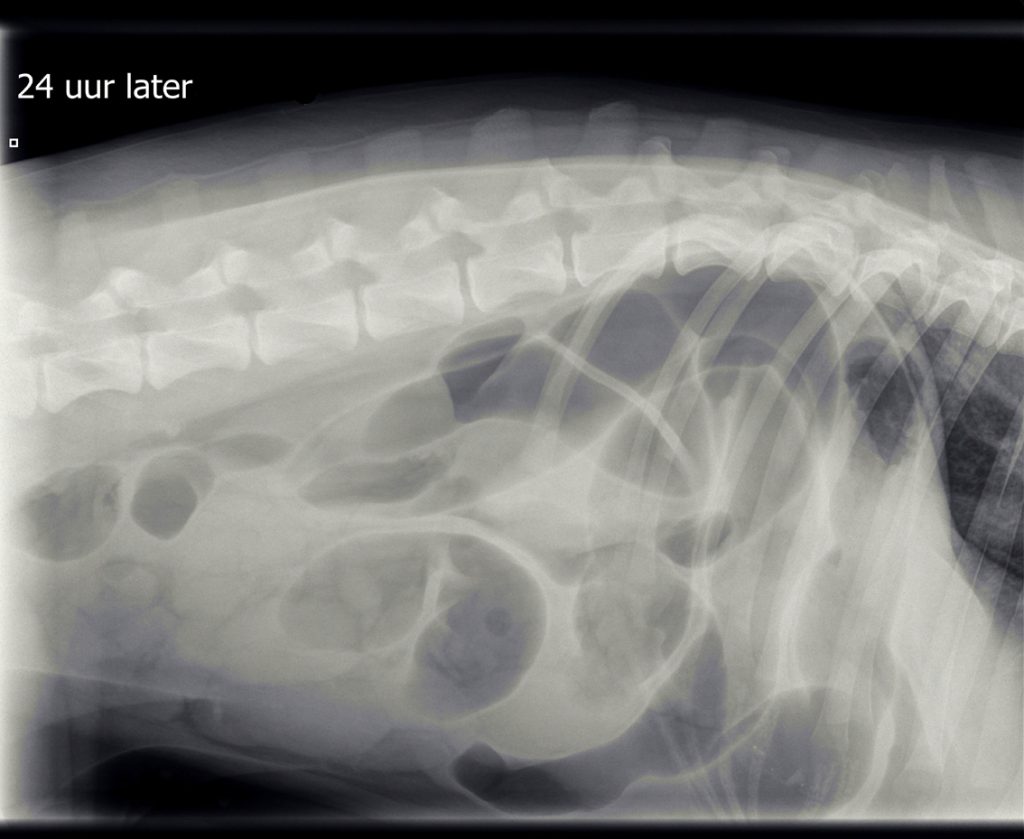

Omdat de hond verder niet ziek was en de buik niet gevoelig, werd besloten om de röntgenfoto’s na een dag te herhalen. Hierop was er geheel geen verbetering zichtbaar in de buik ten opzichte van de dag ervoor.

De hoeveelheid lucht had zich zelfs vermeerderd, wat meer in de richting van een verstopping wees, mogelijk door een vreemd voorwerp. De eigenaren vertelden dat er een latex koetje vermist werd. Helaas is latex meestal niet zichtbaar op een röntgenfoto. De enige mogelijkheid om een verstopping te verhelpen die niet reageert op medicatie, is opereren, dus diezelfde middag werd T-Bone voorbereid voor operatie.